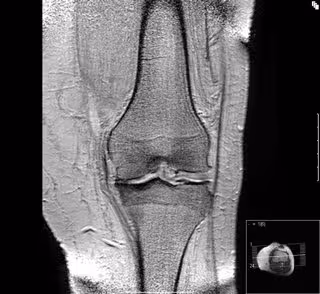

La dieta rica en grasas saturadas y carbohidratos favorece la artrosis

Artrosis de rodilla

Investigadores de la Universidad de Southern Queensland (Australia) han descubierto que un alto consumo de ácidos grasos saturados y carbohidratos pueden acabar debilitando el cartílago de las articulaciones y aumentar el riesgo de artrosis, fundamentalmente en cadera y rodilla.

La función principal del cartílago es sellar los extremos del hueso en las articulaciones y absorber la presión sobre los huesos durante el movimiento, como al caminar. Y, según ha detallado, una dieta con carbohidratos sencillos y grasas saturadas al 20 por ciento fue ya suficiente para provocar cambios en la rodilla.